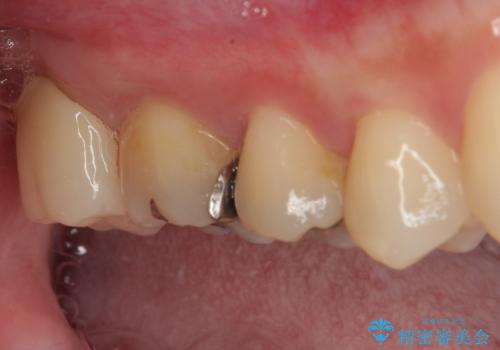

- 元々むし歯があったものの、処置が困難とのことでしたが、矯正治療を終えたので処置をしたいとのことで来院された患者様です。

左右ともに最後臼歯が頬側に顕著に突出しており、むし歯になってしまったことが想像されました。

矯正治療により処置が可能な位置に歯が移動したため、オールセラミッククラウンにて補綴治療を行うこととしました。

歯列が移動したとはいえ、左右ともに後方傾斜しており、むし歯の除去、形成(形を整える)、型取りの全てが非常に困難な処置となりました。